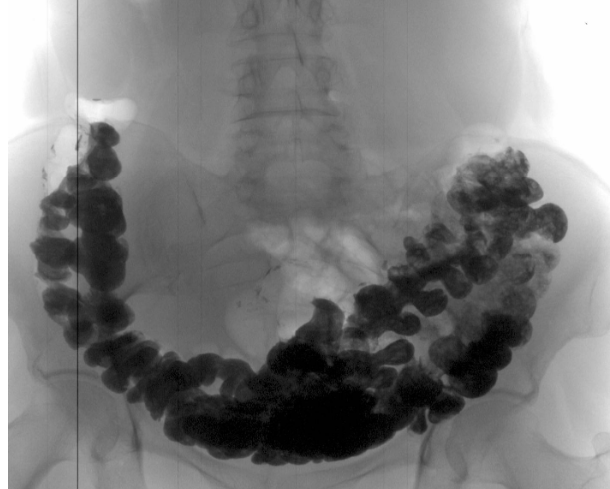

Przyjrzyj się zdjęciom narządów osób, które początkowo miały nieświeży oddech, zaparcia i zgagę, a ostatecznie otrzymały raport patologa.

„Rak jelita grubego u kobiety z częstymi zaparciami”

„USG kamieni kałowych w okrężnicy”

„Stopnie rozwoju raka odbytnicy rozwijającego się w ciągu 1–2 lat”